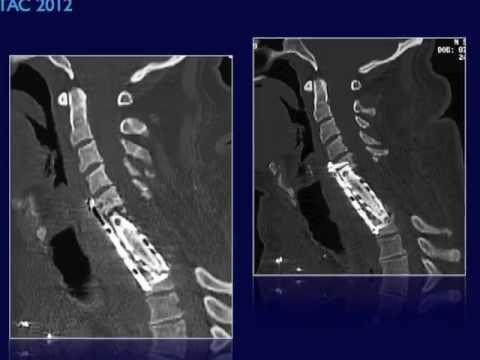

Hellow guys, Welcome to my website, and you are watching Arachnoid Cyst. Microsurgical Fenestration. and this vIdeo is uploaded by remainCAB at 2012-11-10T03:19:33-08:00. We are pramote this video only for entertainment and educational perpose only. So, I hop you like our website.